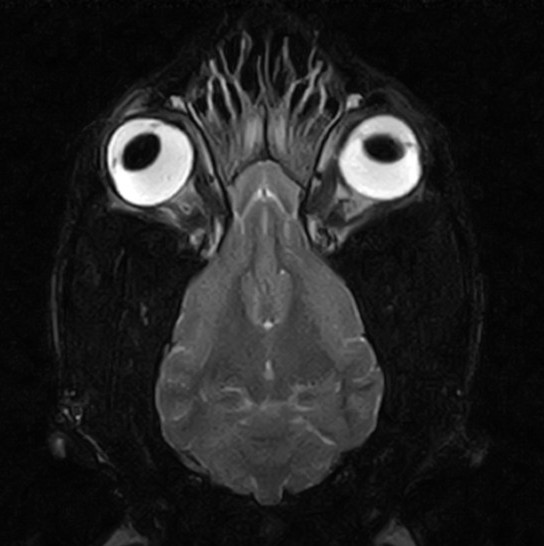

脳の異常を調べるため、MRI検査を実施

脳実質に炎症や腫瘍形成、梗塞所見などを疑う器質的変化は認められず、側脳室拡大など水頭症や脳圧亢進を疑う明らかな所見も認められなかった

中耳や内耳領域にも特異所見は認められず、よって脳内に明らかな異常が認められなかったため「特発性てんかん」と診断